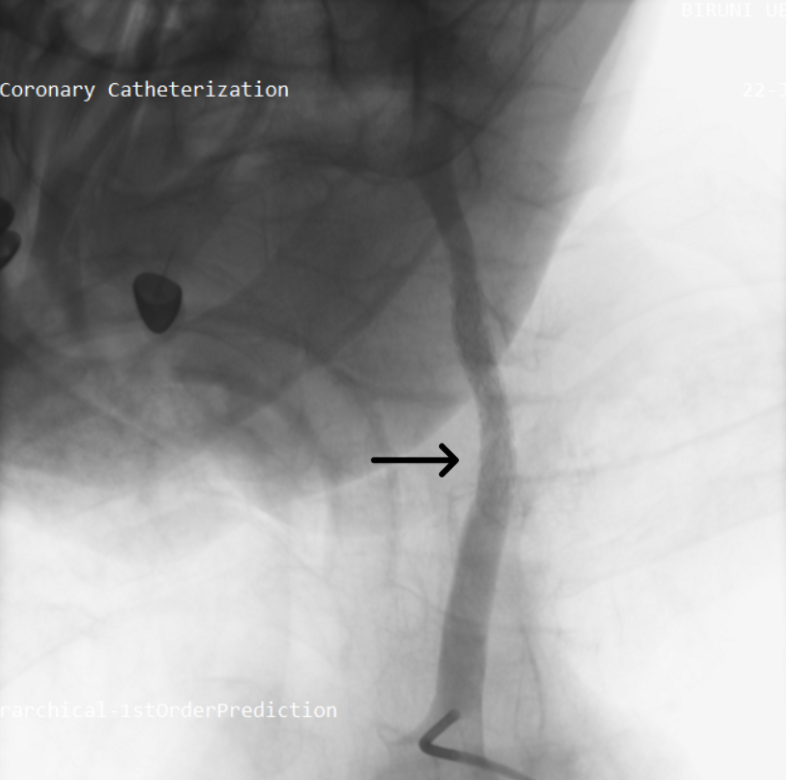

Given the hemodynamic instability, recurrent syncope, and imaging findings suggestive of carotid destruction, a multidisciplinary team involving cardiology, neurology, and oncology recommended urgent digital subtraction angiography (DSA) with therapeutic intent. Right femoral access was obtained, and a 6F Judkins Right 4.0 guiding catheter was advanced into the left common carotid artery. An Amplatz Super Stiff Guidewire (Boston Scientific) was positioned across the lesion, followed by placement of a 6F long sheath to ensure procedural support. DSA revealed active contrast extravasation at the site of tumoral invasion (Figure 1, Video 1).